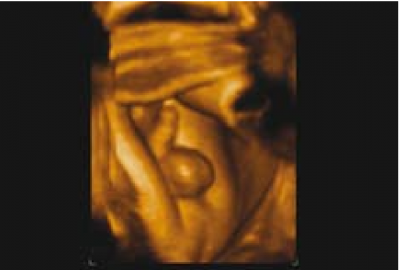

ברונשטיין וחבריו[7] דיווחו שדיוק אבחון מין העובר על ידי אולטרסאונד נרתיקי עולה עם הניסיון, כך שבשנתיים הראשונות לשימוש באולטרסאונד נרתיקי, המין אובחן בדיוק של 76 אחוז ועלה ל-80 אחוז בשנתיים לאחר מכן בין השבועות 13–14 להיריון, ובשבוע 15-16 הדיוק עלה מ-88 אחוז בשנתיים הראשונות לניסיונם ל-96.7 אחוז בשנתיים לאחר מכן. בעבודה זו, מין זכר נקבע על סמך הדגמת מבנה דמוי כיפה (Dome sign) המייצג שק אשכים (תמונה 3) בעוד מין נקבה נקבע על סמך הדגמת שניים או ארבעה קווים מקבילים (Parallel lines) המייצגים את השפתיים הקטנות והגדולות (תמונה 4) . סימנים סונוגרפיים נוספים בעבודה זו[7] היו הדגמת קו אקוגיני הנמשך מבסיס ועד קצה איבר המין הזכרי ומייצג קו האמצע של הפניס (תמונה 5) וכיוון הפאלוס העוברי (כלפי מעלה מייצג זכר וכלפי מטה נקבה).

אולטרסאונד תלת ממדי - מנסיוננו, שימוש באולטרסאונד תלת ממדי אינו מוסיף משמעותית לאבחון מין העובר, במיוחד בטרימסטר הראשון ותחילת הטרימסטר השני ולעיתים יכול אפילו להטעות (תמונה 6). Benoi[9] ואחרים[31][32] הגיעו למסקנה שאכן התלת מימד אינו עוזר לאבחון מין העובר אך השימוש בחתכים (Sectional planes) לעיתים יכול לעזור על ידי הצגת החתך הסגיטלי האמצעי ביתר קלות ובכך לעזור לאבחון מין העובר. בטרימסטר השני והשלישי התלת מימד יכול לעזור בהצגת איברי המין להורים בצורה יותר משכנעת (תמונות 7 ו-8). בחלק מהמקרים עם מומים באיברי המין החיצוניים, התלת מימד יכול להדגים את המום ולעזור להגיע לאבחנה, כפי שנדון בהמשך.